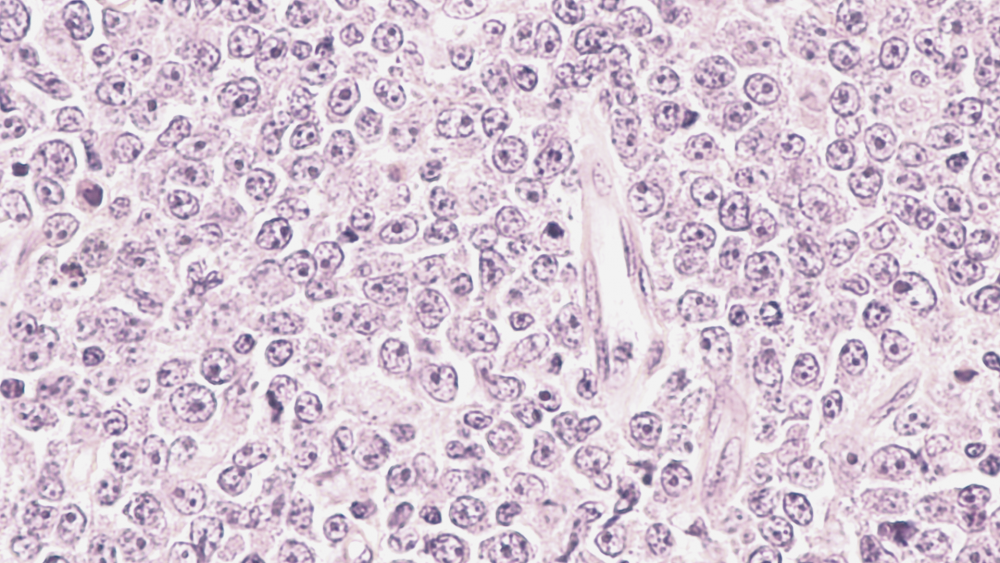

Острые лейкозы

Острые лейкозы развиваются стремительно, в крови человека за короткий срок концентрируется большое количество атипичных клеток.

Хронические лейкозы

Это клональное опухолевое новообразование, которое обусловлено злокачественным перерождением ранних гемопоэтических (кроветворных) клеток и характеризуется постепенным распространением и разрастанием атипичных клеток.

Лимфома Ходжкина

Лимфома — это злокачественное заболевание лимфатической системы, при котором происходит увеличение лимфатических узлов и появление очагов во внутренних органах, зачастую не относящихся к лимфатической системе, из-за того что в них накапливаются опухолевые лимфоциты.

Неходжкинские лимфомы

Неходжкинские лимфомы (НХЛ), в противоположность лимфоме Ходжкина, часто расположены вне лимфатических узлов и склонны к метастазированию, редко ограничиваются одной областью, поражая часто костный мозг и печень.